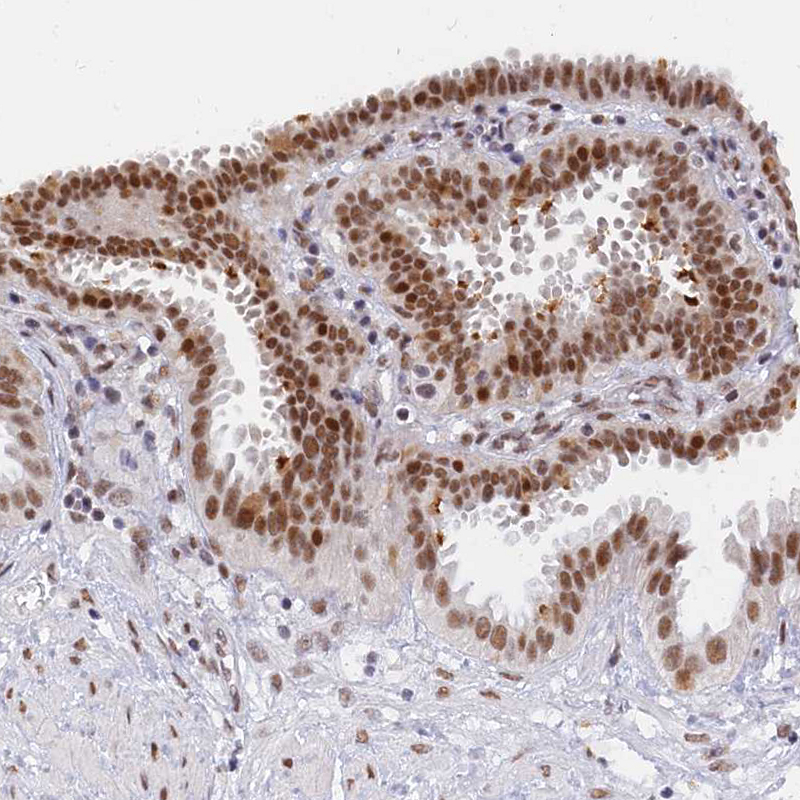

Immunohistochemical staining of human fallopian tube shows moderate to strong nuclear positivity in glandular cells.